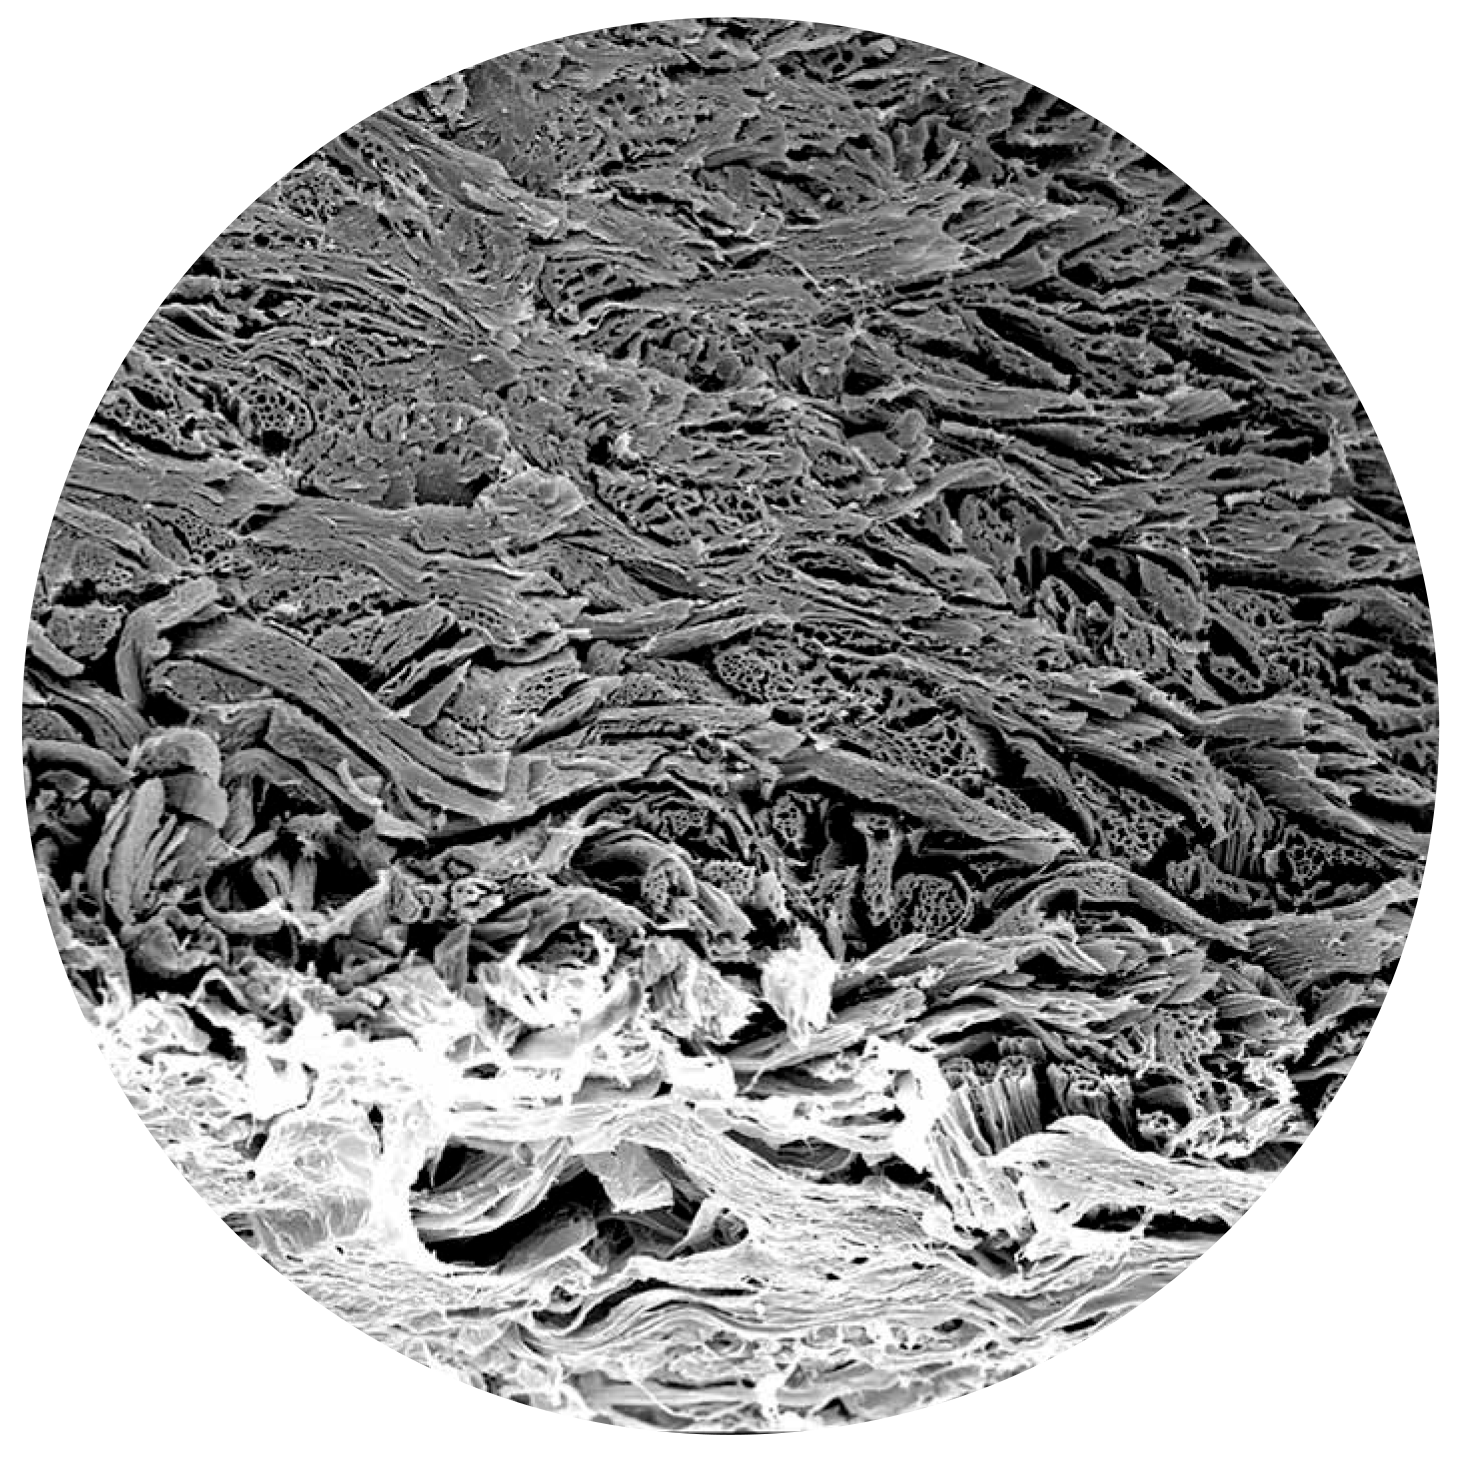

Mikroyapı (SEM Görüntüleri)

biocade®’in homojen ve poröz kollajen mikroyapısı, hücre migrasyonu ve doku entegrasyonunu destekleyen biyolojik performansın temelini oluşturur.

biocade® SEM görüntüsü 1 biocade® SEM görüntüsü 2 biocade® SEM görüntüsü 3